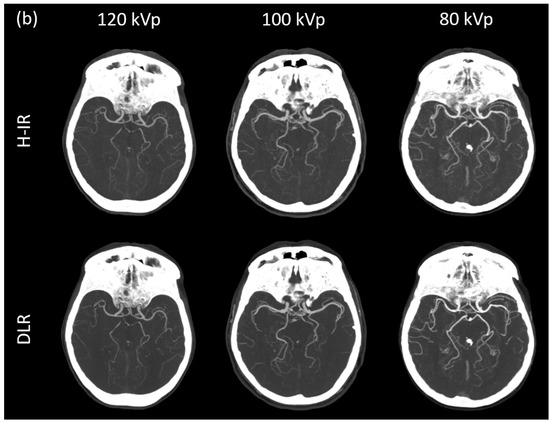

3.3.1. Image Signal Fluctuation with DLR vs. H-IR

3.3.2. Comparison of the Two Reconstruction Techniques at Constant kVp Value

3.3.3. Comparison of Low kVp plus DLR vs. Standard kVp plus DLR

3.3.4. Comparison of Low kVp plus DLR vs. Standard kVp plus H-IR

3.4. Qualitative Image Analysis